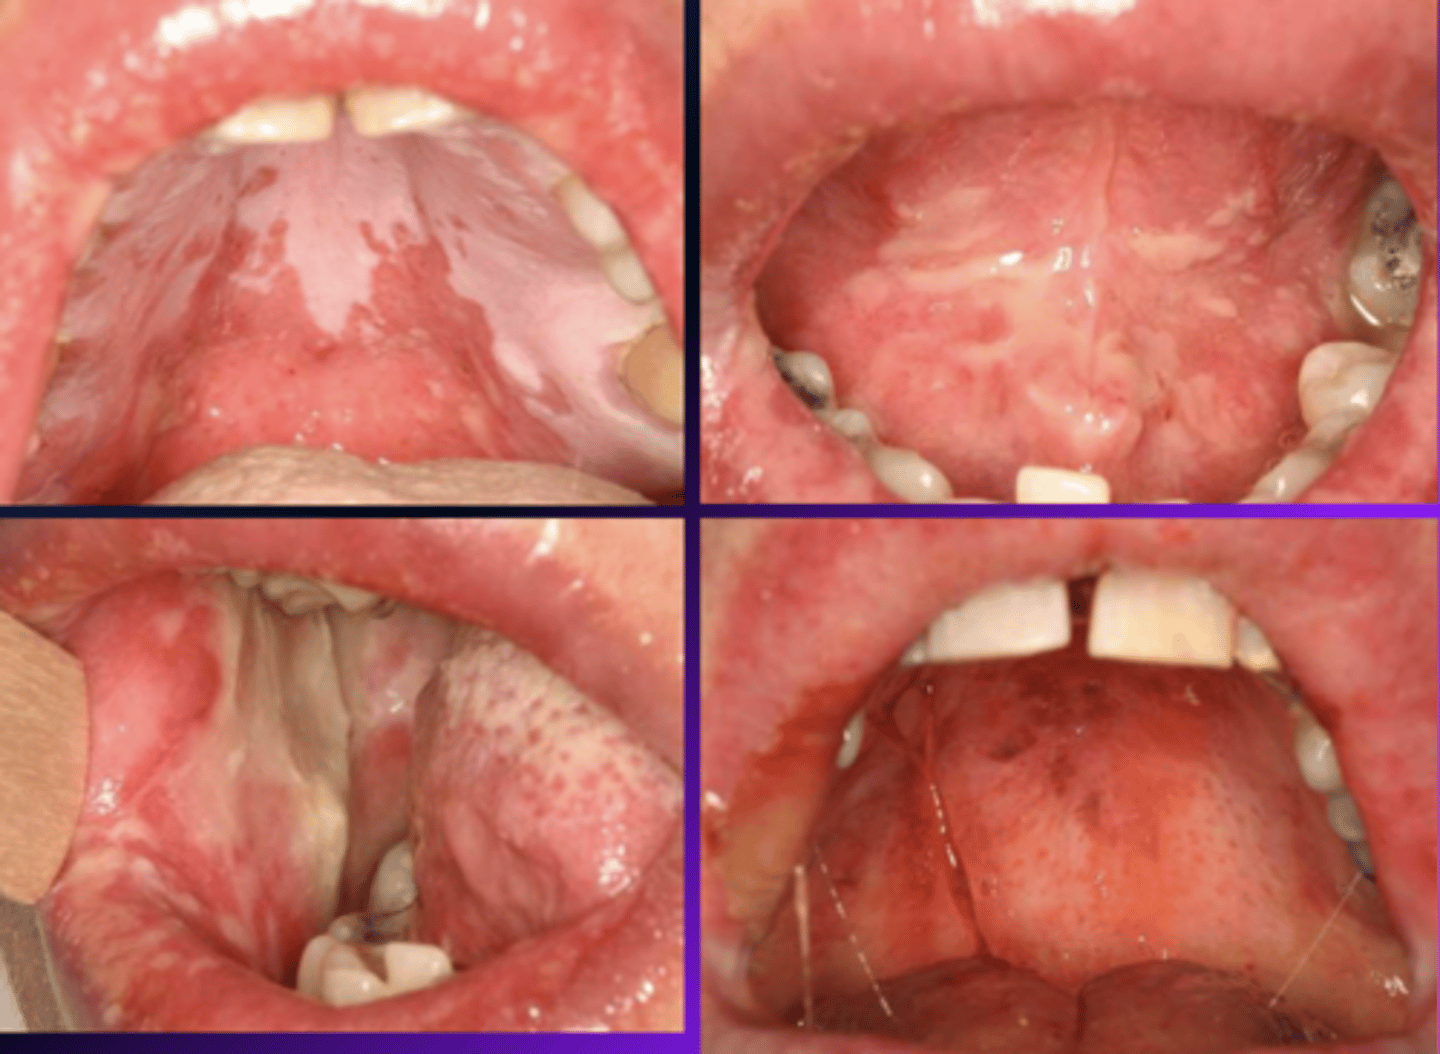

lichen planus (reticular)

What condition?

- Often asymptomatic

- Posterior buccal mucosa (bilaterally)

- Lacy white striations (Wickham striae)

Wickham striae (lacy white striations) is a classic feature of what condition?